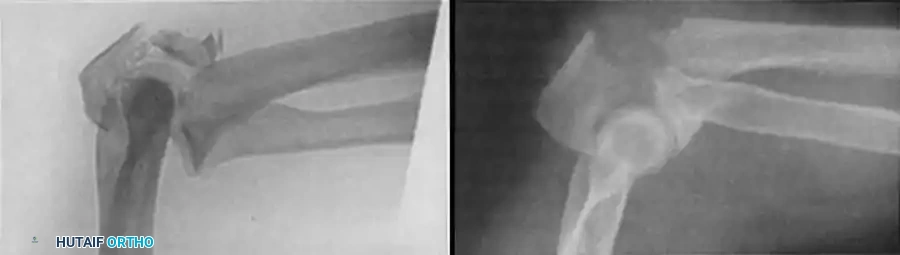

4. Plate Osteosynthesis

If comminution with bone loss prevents the use of a tension band compression technique—due to the risk of shortening the olecranon and narrowing the greater sigmoid notch—plate fixation is mandatory. Plating is also the gold standard for Monteggia fracture-dislocations, oblique fractures extending distally, and fractures involving the coronoid process.

Construct Design:

Hand-contoured reconstruction plates or modern, anatomically precontoured locking plates (e.g., Acumed, Synthes) provide rigid, stable fixation. The plate is applied to the posterior (tension) surface of the ulna.

Clinical Pearl: When applying a posterior plate, use unicortical screws for the holes immediately adjacent to the articular surface to avoid inadvertent penetration into the radioulnar or ulnohumeral joints.

Fig. 54-58 A-C, Plate fixation can be used to stabilize comminuted fractures of the olecranon. Precontoured plates offer excellent proximal purchase with locking screws. (From Heim U, Pfeiffer KM: Internal fixation of small fractures, 3rd ed, Berlin, 1988, Springer-Verlag.)

🔪 Surgical Technique: Plate Fixation

- Reduction: Restore the articular block. Temporary K-wires can be used to hold comminuted articular fragments.

- Plate Application: Apply a precontoured olecranon plate to the posterior aspect of the proximal ulna. The proximal portion of the plate often wraps over the tip of the olecranon to capture the proximal fragment with multiple locking screws.

- Fixation: Secure the plate distally to the ulnar shaft using standard cortical or locking screws. If an oblique fracture line is present, a lag screw can be placed independently or through the plate to achieve interfragmentary compression.

- Bone Grafting: If significant metaphyseal void exists after elevating impacted articular fragments, autogenous cancellous bone graft or allograft should be packed into the defect prior to final plate tightening.